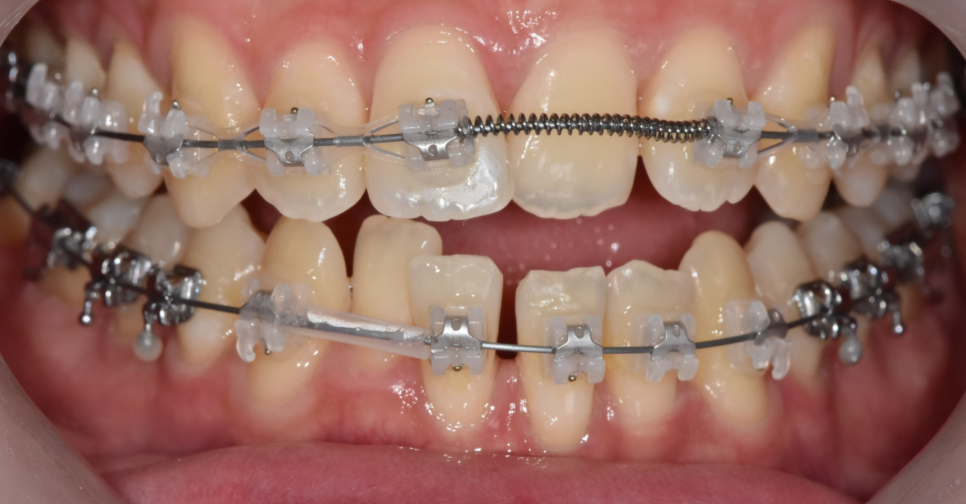

250307 위 아래 앞니가 뒤바뀐 부위

치아 들어가고 나오고를 일정하게 맞춰달라는

말씀을 해주셨어요.

앞니 물림이 뒤바뀐 부분을

"해소"해달라고 하셨습니다.

아래쪽 앞니가 앞으로 나와

치아가 튀어나와 보이는 느낌이라고 하시면서 말이죠.

#21 (왼쪽 윗앞니)이 아랫니보다 안쪽으로 물리고 있어서

전치부 반대교합(Anterior Crossbite) 상태

아래 앞니(#31, #41)는 공간이 벌어져 있으면서

앞으로 나와 있는 모습이었습니다.

쉽게 말하면 위 아래 치아가 거꾸로 물리는데...

일부 치아만 반대로 물리는 상황

이런 것을 부분적 반대교합이라 말합니다.